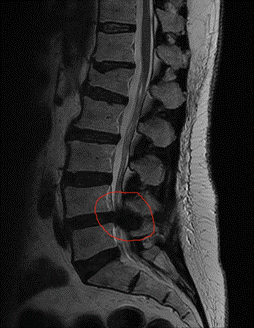

De klachten van een lumbale kanaalstenose worden veroorzaakt door een vernauwing van het onderste gedeelte van het wervelkanaal. Deze vernauwing is vaak het gevolg van artrose (slijtage van de gewrichten binnen de wervelkolom). Artrose is een normaal verouderingsverschijnsel dat bij iedereen in meer of mindere mate optreedt. Als reactie op artrose verdikken de wervels en de bindweefselbanden van de wervelkolom. Bij slijtage/afplatting van de tussenwervelschijven kunnen deze gaan uitpuilen in het wervelkanaal. Al deze veranderingen gaan ten koste van de wijdte van het wervelkanaal (zie figuur 1 en 2). Daardoor blijft er minder ruimte over voor de zenuwwortels die vanuit het wervelkanaal/de rug naar de benen lopen.

Een MRI scan van de onderrug kan aantonen of er ook daadwerkelijk sprake is van een abnormale vernauwing van het wervelkanaal. Bij patiënten die geen MRI scan kunnen ondergaan, bijvoorbeeld omdat zij een pacemaker hebben, is het maken van een CT scan (met contrastmiddel) een goed alternatief.

MRI’s met een vernauwing van het wervelkanaal (”umbale stenose’)